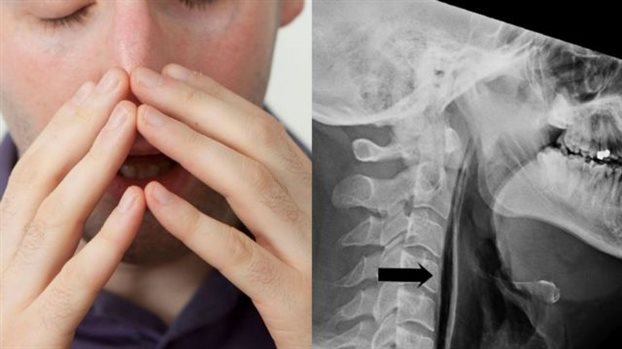

Ένας 34χρονος άντρας, του οποίου το όνομα δεν έχει δοθεί στη δημοσιότητα, υπέστη ρήξη στον λαιμό όταν αποπειράθηκε να καταπνίξει το φτάρνισμά του.

Σύμφωνα με την έκθεση των ιατρών στην επιθεώρηση British Medical Journal Case Reports ο 34χρονος, μεταφέρθηκε στα Επείγοντα όταν μετά από ένα «πνιχτό» φτάρνισμα εκδήλωσε αλλαγές στη φωνή του, πρήξιμο στον αυχένα και πόνο κατά την κατάποση. Παράλληλα ο ίδιος ανέφερε ότι τη στιγμή του φταρνίσματος ένιωσε σαν κάτι να έσκασε στον αυχένα του και αμέσως μετά δυσκολευόταν να μιλήσει.

Οι ακτινογραφίες του έδειξαν ότι υπήρχαν μικρές φυσαλίδες αέρα στους ιστούς του λαιμού καθώς και στον αυχένα, στη βάση του κρανίου. Τα ευρήματα αυτά ερμηνεύτηκαν από τους γιατρούς ως ρήξη στο πίσω μέρος του λαιμού τού 34χρονου, η οποία προκλήθηκε από την ισχυρή πίεση που προκάλεσε ο παγιδευμένος αέρας.